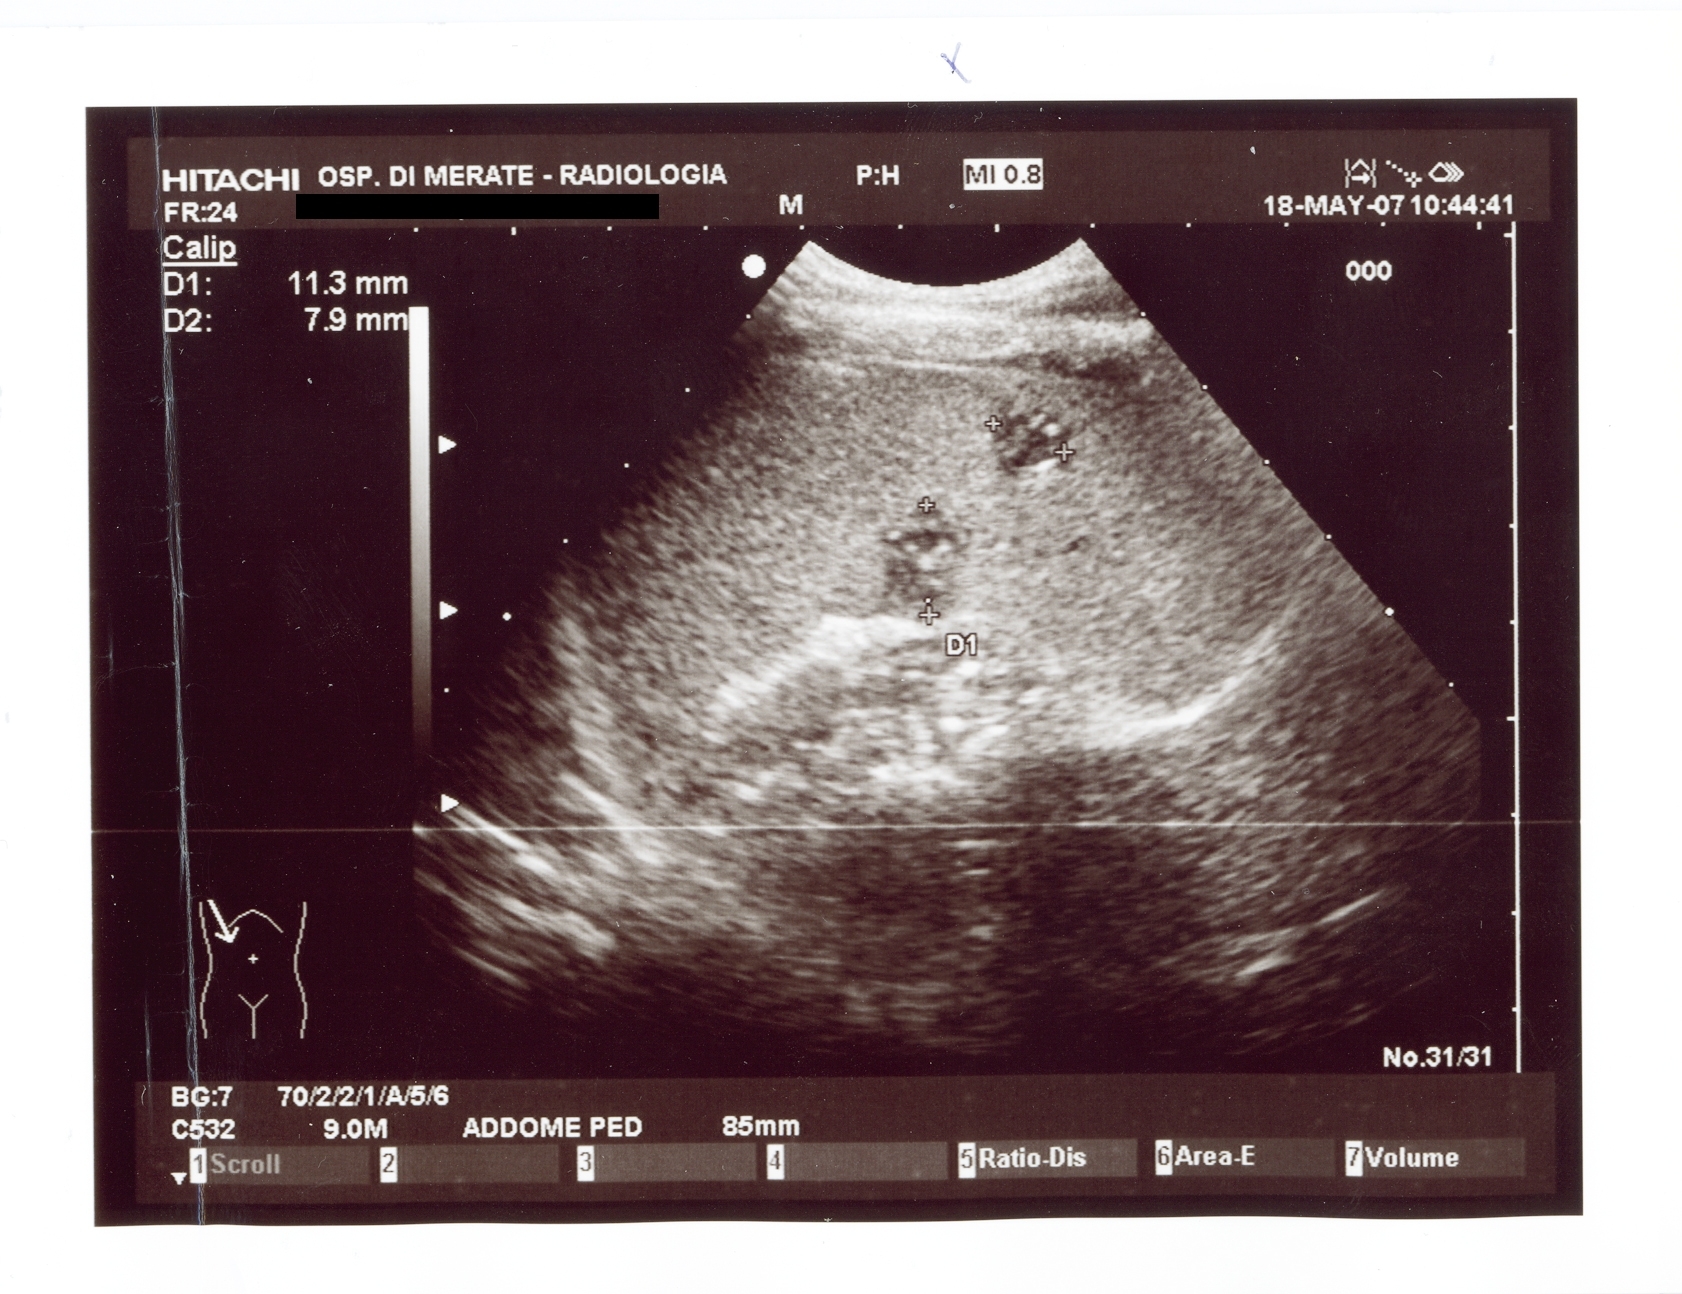

Il follow-up di G. � durato per un anno, in cui il piccolo � cresciuto in modo soddisfacente e non ha presentato alcun problema clinico; l'ultima ecografia (dopo 6 mesi di follow-up) mostrava un'obiettivit� epatica perfettamente regolare e a livello splenico due piccole lesioni calcificate (Figura 2).

Figura 2. Ecografia addome; in particolare nel parenchima del parenchima splenico sono ancora riconoscibili tre piccole lesioni rotondeggianti del diametro di 11, 8 e 6 mm rispettivamente.